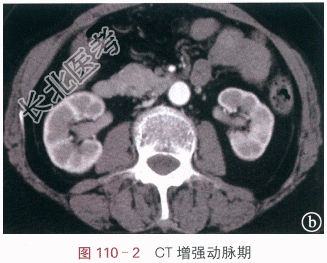

读片分析:图110-1IVP示右侧肾下盏及肾盂内有充盈缺损影,边缘欠规则;图110-2(动脉期)与图110-3(静脉期)示CT增强扫描后肾盂内病灶有强化,CT值分别约为91.3Hu和102.1Hu,平扫时(未提供)病灶CT约为30.6Hu;图110-4CTU示肾盂内充盈缺损。结合病史,可知患者为肾盂癌。